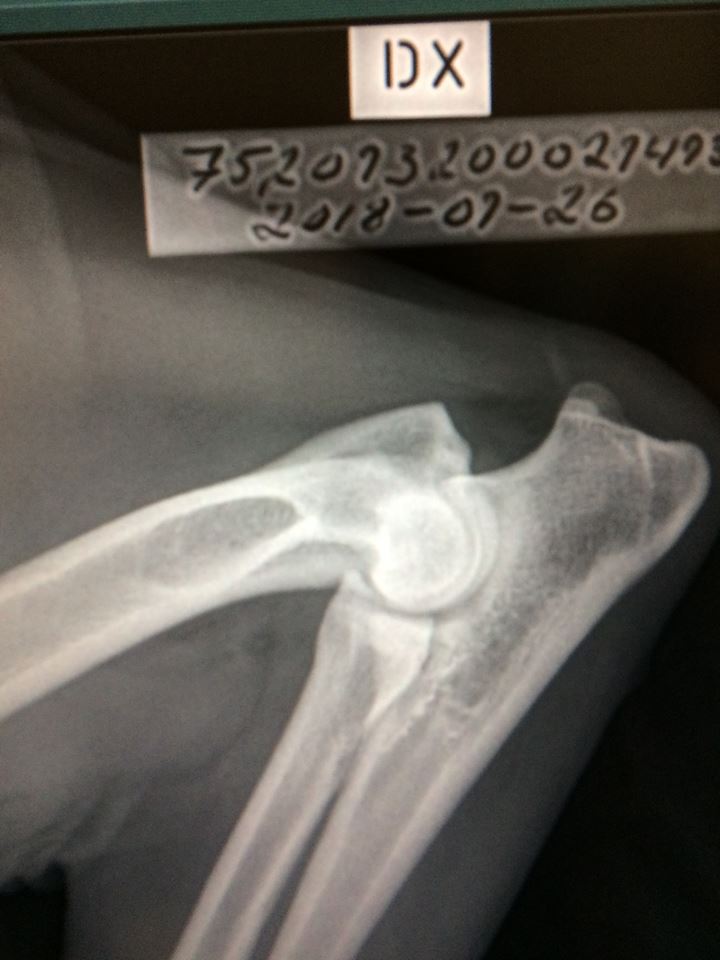

Signes Högra armbåge. avläst med 0